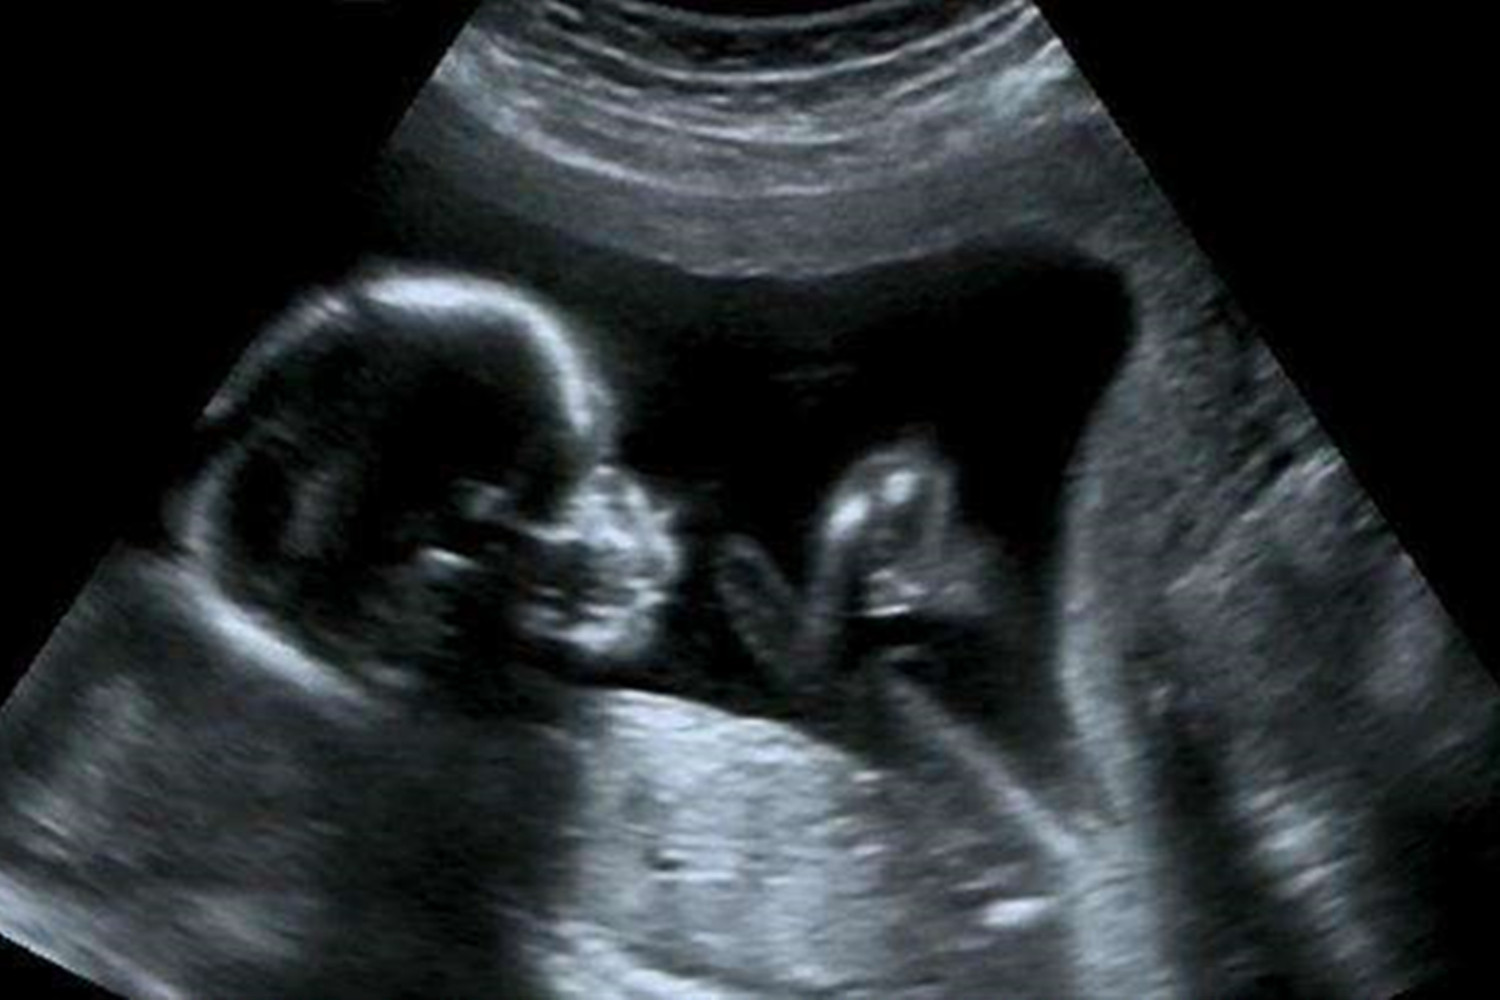

B超检查可以说是判断胎儿性别最准确、最科学的方式之一了,它可以透过孕妇的肚子观察腹中胎儿的生殖器官。

但是,大家也别把B超检查“神化”,它的影响因素较多,也是有一定概率导致判断错误的。

缜密点说,B超只能是准确性相对较高,但不能完全作为结论。

大家应该都见过B超影像,画面灰蒙蒙的,呈现黑白色。

作为非专业人士的我们,可能最多就只能看出胎儿的四肢和头部了,其他部分根本分辨不出。